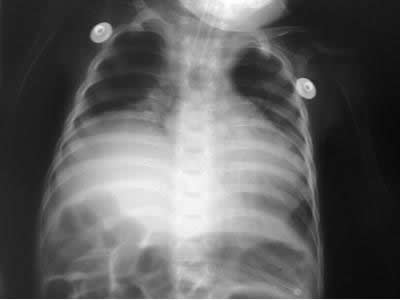

Radiología de tórax Post operatorio

Rx. torax 48 horas del post operatorio:

• Observamos un diafragma derecho mas plano, mayor cavidad pleural, totalmente ocupada por pulmon, la silueta cardiaca ahora mas central.

Rx post operatorio eventracion diafragma

A las 72 horas del post operatorio el lactante fue extubado y su egreso de UTIP, ocurrió al octavo dia del postoperatorio, mas pronto de lo esperado.